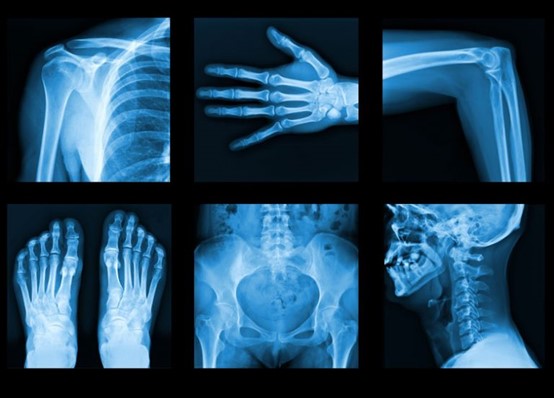

X-ray

X-ray, is a penetrating form of high-energy electromagnetic radiation. Most X-rays have a wavelength ranging from 10 picometers to 10 nanometers, corresponding to frequencies in the range 30 petahertz to 30 exahertz (30×1015 Hz to 30×1018 Hz) and energies in the range 145eV to 124 keV. X-ray wavelengths are shorter than those of UV rays and typically longer than those of gamma rays. In many languages, X-radiation is referred to as Röntgen radiation, after the German scientist Wilhelm Conrad Röntgen, who discovered it on November 8, 1895 He named it X-radiation to signify an unknown type of radiation. X-rays are generated via interactions of the accelerated electrons with electrons of tungsten nuclei within the tube anode. There are two types of X-ray generated: characteristic radiation and bremsstrahlung radiation. <br /> The most familiar uses are: <br /> X-rays can be used to treat tumors in the human body. According to scientists, when the human body is exposed to the right amount of X-rays, this action is capable of destroying certain tumors in the body. Scientists say if this is done very well, the tumors will be destroyed by the X-rays and no harm will be done to the surrounding tissues. Over the years, X-rays have been used extensively to treat people suffering from certain types of tumors. Because of X-rays, doctors are able to easily detect things such as a bone fracture or sprain in the body. This would have been next to impossible in the absence of X-rays. Can you imagine how difficult it would have been for doctors to check for broken bones in the body without the use of X-rays? But thanks to X-rays, these things are now pretty simple.x-rays are not only used in the destruction of malignant tumors, but they are also used by doctors to treat leukemia. Doctors use X-rays to examine the breast to look for breast cancer. X-rays do not only spot cancers, but they can also be used to -stop the growth of cancer cells. The right amount of X-rays introduced to the body can effectively destroy cancer cells growing in the body. X-rays can also be used to photograph the teeth and detect any abnormal growth of teeth. <br /><br /><br />بواسطة م.م. أيلاف مهدي